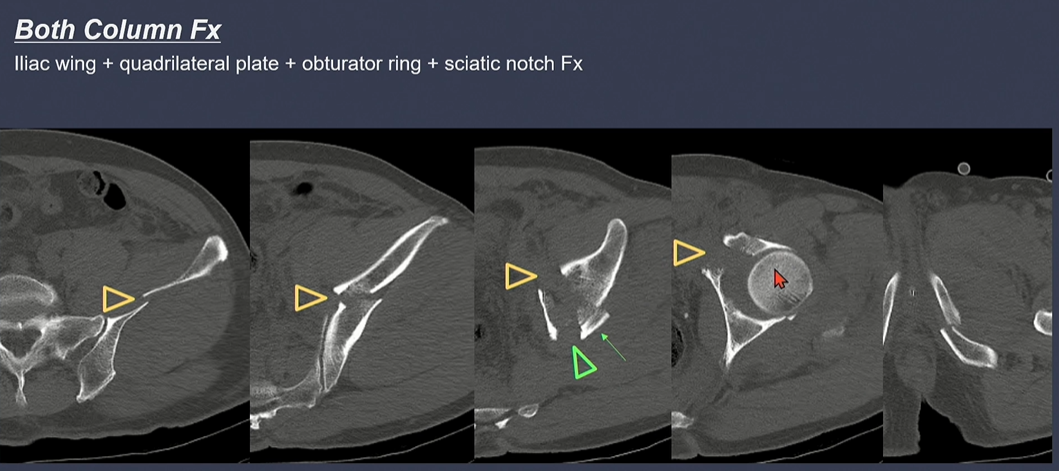

CT상 골절선 확인. 가장 좌측 iliac wing, 중간 사진은 Quadrilateral plate에 골절선이 있음.

노란색 화살표: anterior column + 녹색 화살표 posterior hemitransverse